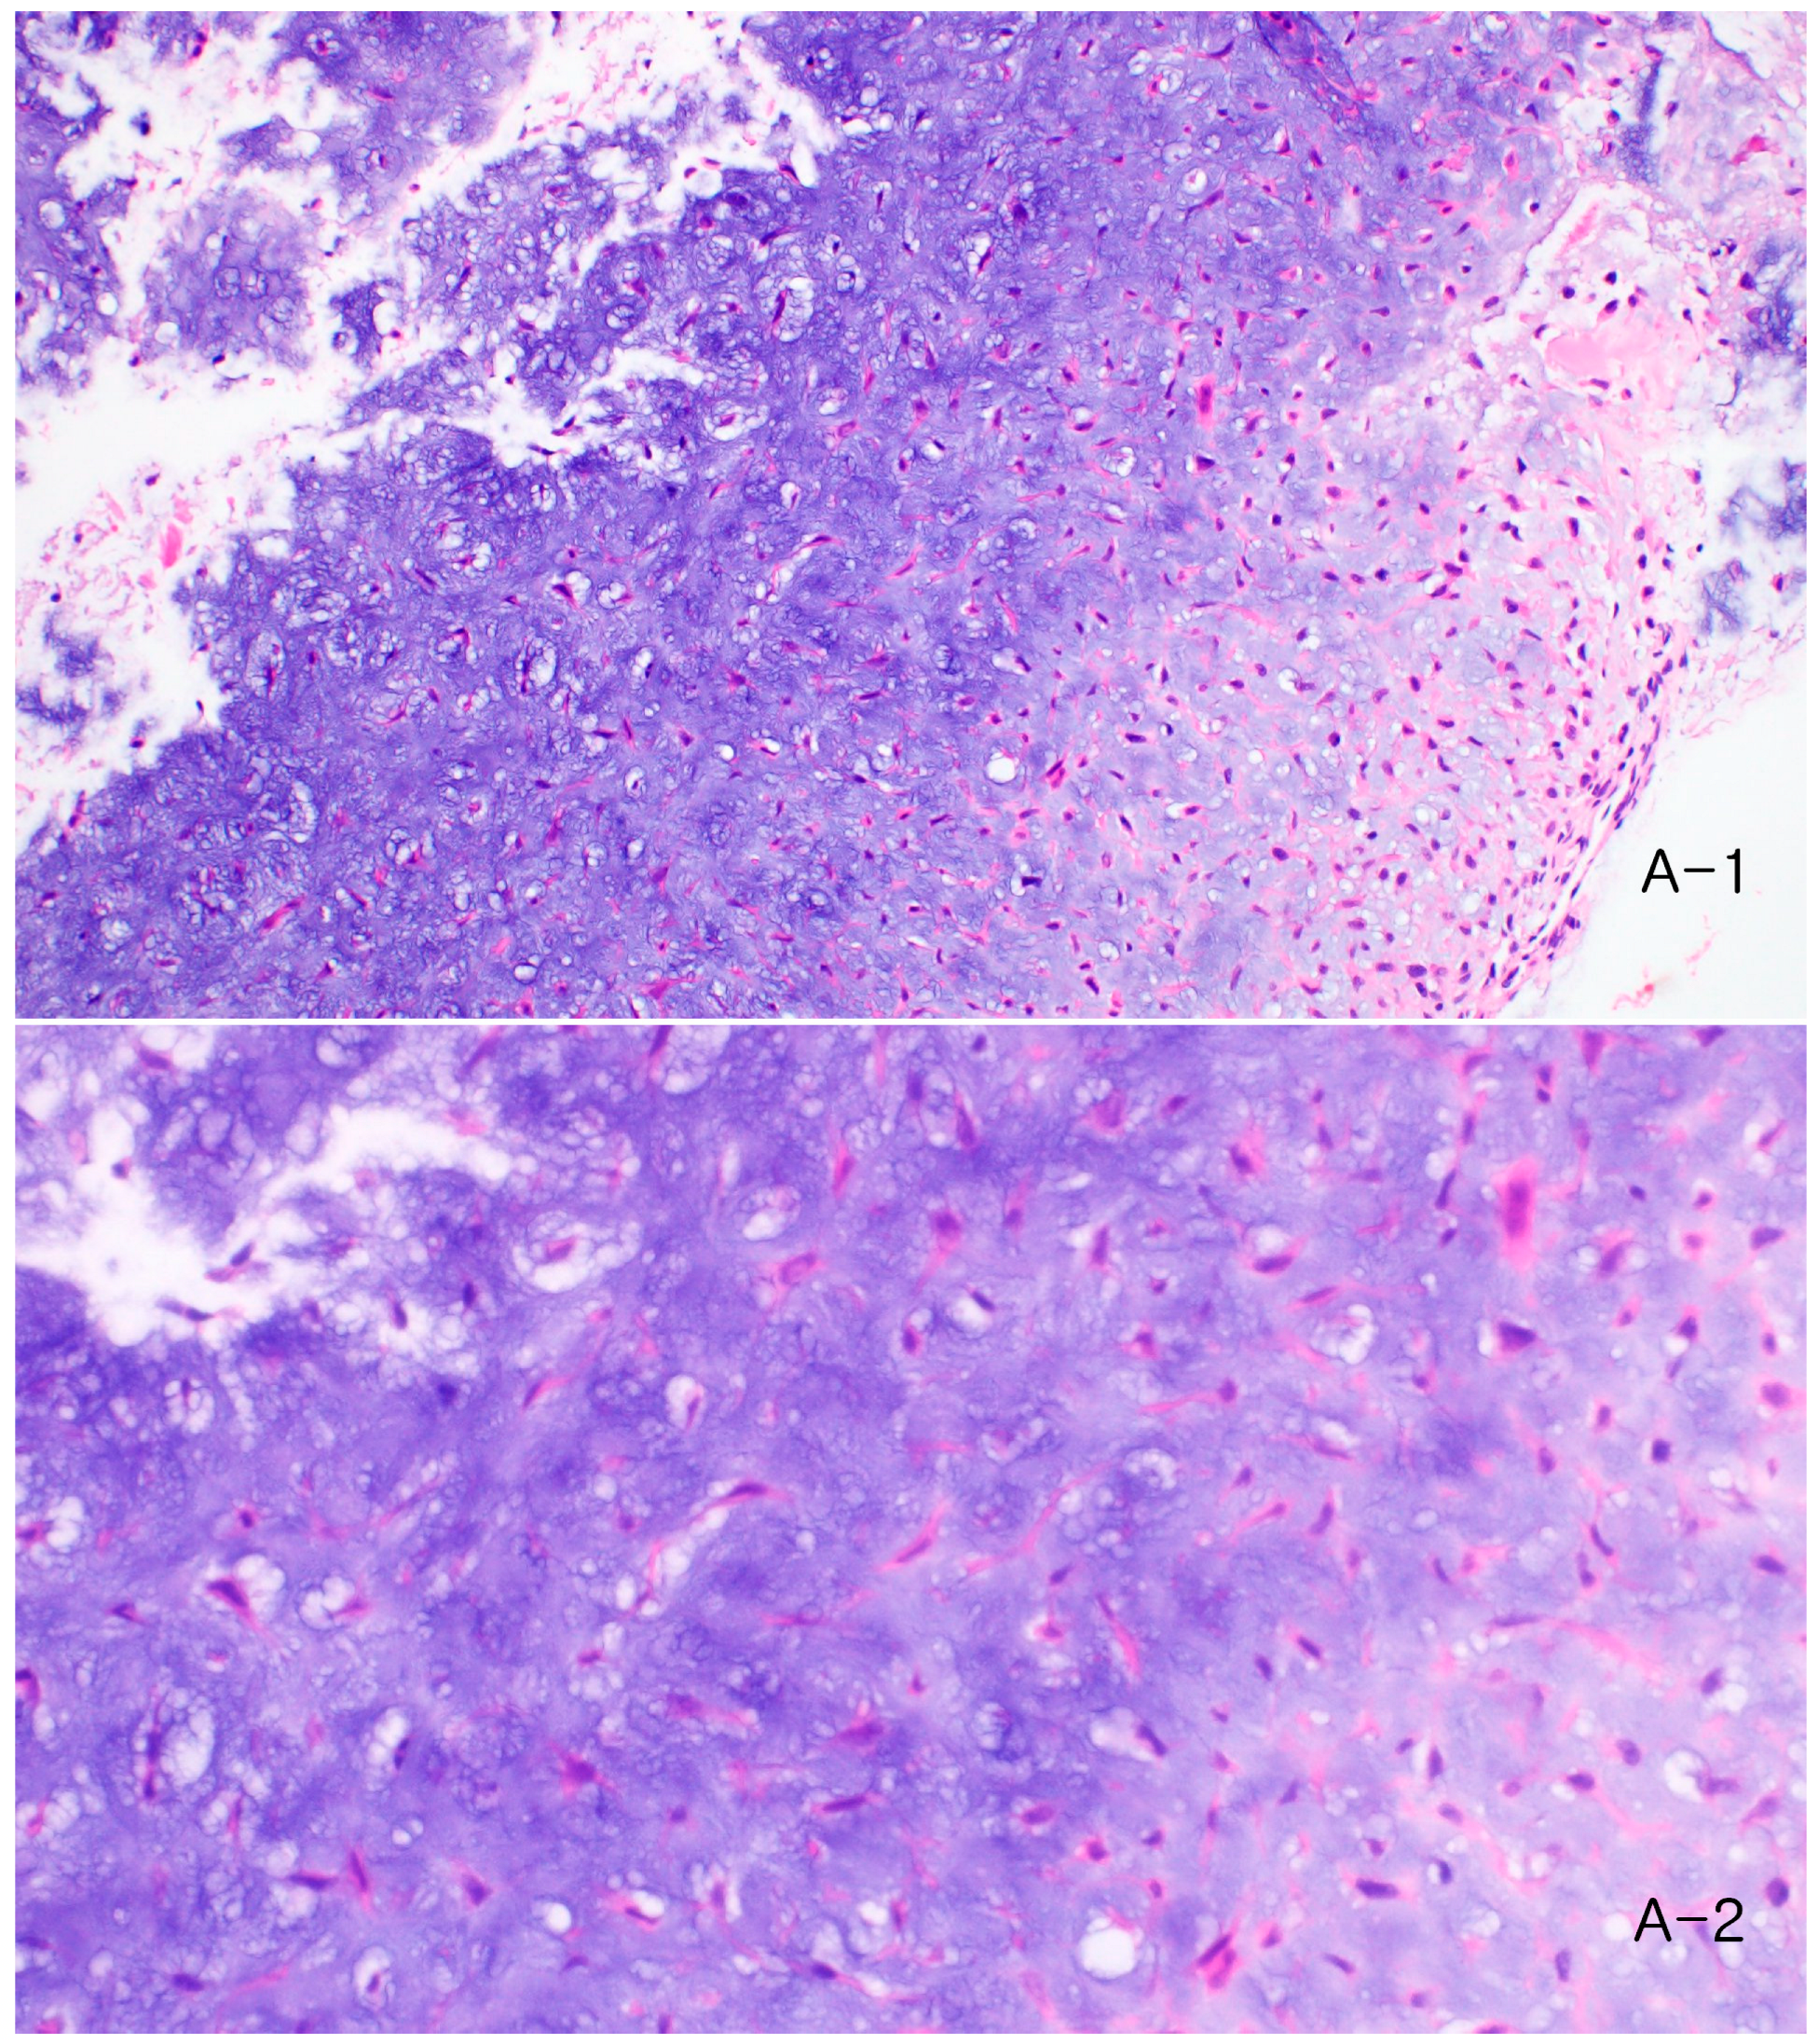

Recurrent Chondromyxoid Fibroma of the Second Toe Distal Phalanx Treated with Distal Phalangectomy: A Case Report

2. Case Report